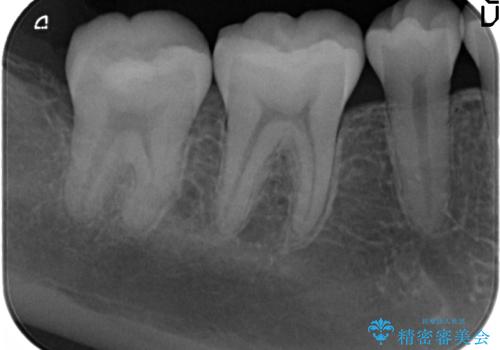

- 笑った時に見える銀歯を外したいと希望され来院されました。

銀歯の下には初期の虫歯も見られたので、除去後精密なシリコン印象を行いセラミックインレーを製作しました。